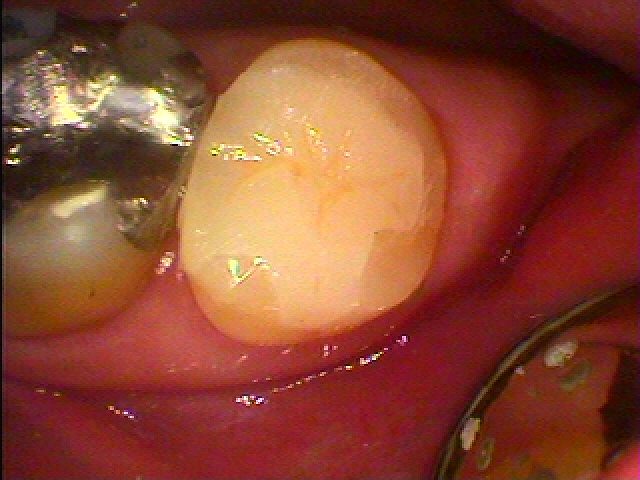

本来の歯のようにきれいに仕上がりました

喜んでいただきました

年々、セラミックも耐久性が向上して安心なものへとなってきました